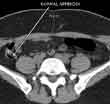

With CT scanning, numerous x-ray beams and a set of electronic x-ray detectors rotate around you, measuring the amount of radiation being absorbed throughout your body. At the same time, the examination table is moving through the scanner, so that the x-ray beam follows a spiral path. A special computer program processes this series of pictures, or slices of your body, to create two-dimensional cross-sectional images, which are then displayed on a monitor.

CT imaging is sometimes compared to looking into a loaf of bread by cutting the loaf into thin slices. When the image slices are reassembled by computer software, the result is a very detailed multidimensional view of the body's interior.